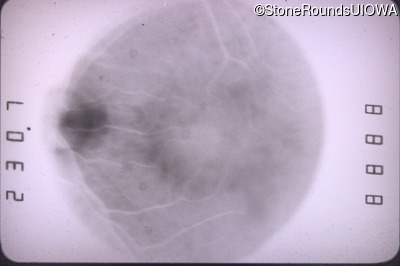

Fundus Photography - Left - 20/60 +2

Exemplar